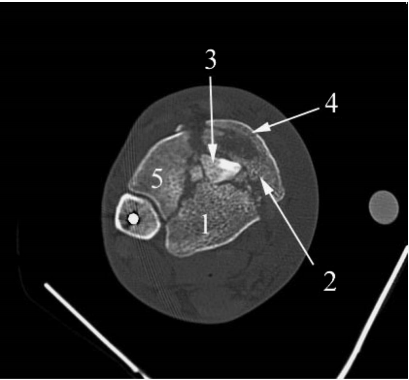

在充分显露关节面直至胫骨远端内侧肩部后,骨折块的复位通常按照从后外侧 > 后内侧 > 中央 > 前侧 > 前外侧的顺序进行(图 5)。通过清除血肿、碎屑和早期骨痂可以进一步改善关节面的可视化。在此过程中应注意不要移除任何关节骨块。通过将前外侧骨块以其韧带附着点为轴向外旋转,可以直接到达关节骨块和干骺端。如果存在一个与后外侧关节骨块相连的较大的后侧皮质棘突,可以将此骨块复位到完整的胫骨上,并用经皮斜行从前侧胫骨置入后外侧骨块的克氏针固定。假设可以获得并维持足够的后侧复位,则关节面可以基于此后外侧骨块进行重建。然而,如果无法实现后侧复位或复位不准确,将导致关节复位不良。在这些情况下,应首先重建关节面,然后非常小心地将其固定到剩余的胫骨上,以维持矢状面对线。

图 5. 轴向计算机断层扫描图像,数字表示通过前外侧显露进行关节骨块复位的顺序:(1) 后外侧;(2) 后内侧;(3) 中央;(4) 前侧;和 (5) 前外侧。